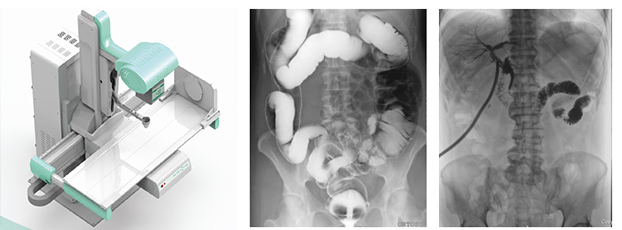

多功能動態(tài)dr由動態(tài)平板探測器、高壓發(fā)生器、球管、運(yùn)動機(jī)架、計(jì)算機(jī)與圖像處理與傳輸系統(tǒng)組成,與傳統(tǒng)數(shù)字化X線攝影技術(shù)相比,動態(tài)多功能dr攝影能在一個(gè)時(shí)間單位內(nèi)低劑量高速獲得多幀X線影像,通過圖像算法處理系統(tǒng)后,極速輸出一段連續(xù)動態(tài)影像(運(yùn)動),實(shí)現(xiàn)所見即所得。

多功能動態(tài)dr是集合拍片,透視,造影三種功能為一體的設(shè)備。可以對特殊病灶部位進(jìn)行高速實(shí)時(shí)點(diǎn)片,捕獲高清病灶圖,降低了漏診誤診率。特別是對不能配合的患者,也能進(jìn)行快速高效的檢查,大大減輕了患者的痛苦。